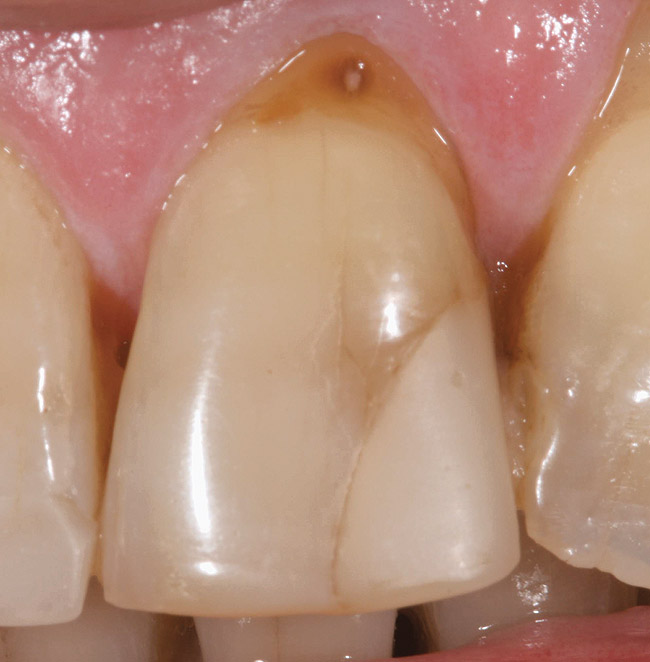

Stage 2 Demineralization (D2)

D2 root-surface lesions (Figure 3) are characterized by the dull surface demonstrated with D1 root-surface lesions. In addition, the surface feels sticky and somewhat soft when palpating with the side of the explorer. The examiner may notice that the root surface slightly resists gentle exploration over the root surface with the side of the explorer. Color changes in D2 root-surface lesions may range from dark yellow to orange/light brown. No cavitation of the root surface exists. The recommended treatment for D2 root-surface lesions includes remineralization with products (pastes and varnishes) containing fluoride, calcium, and phosphate. If the area is in the esthetic zone, the patient may request restoration, despite intact root structure.

It is common for practitioners to press the tip of the explorer into these root surfaces and decide to restore these “carious” areas. When pressing an explorer into a D2 root surface, a clinician may feel a definite softened surface or a “stick.” It is vital to either use the side of the explorer or visual inspection when determining these lesions. Aggressive exploration with the tip of the explorer may cavitate these root surfaces, which can lead to mechanical damage of the root surface and a decrease of the likelihood of successfully remineralizing the surface.

Figure 3  This root surface has a dull surface and is discolored. This indicates the progression of the demineralization/caries process. No cavitation has occurred due to this process. This root surface will feel slightly tacky and softened when exploring with the side of the explorer.

Figure 3